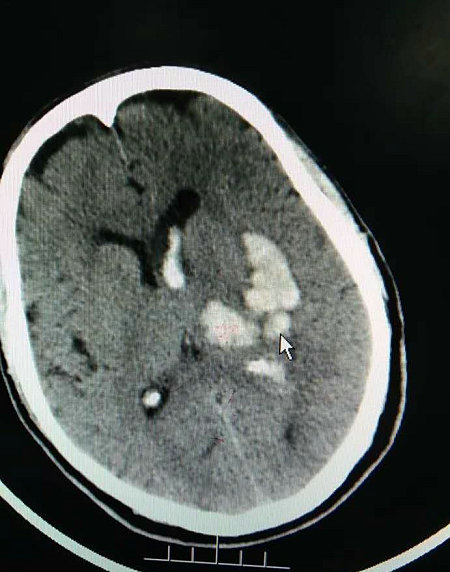

▲ 术前